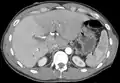

The diagnosis of liver disease is made by liver function tests, groups of blood tests, that can readily show the extent of liver damage. If infection is suspected, then other serological tests will be carried out. A physical examination of the liver can only reveal its size and any tenderness, and some form of imaging such as an ultrasound or CT scan may also be needed.[63] Sometimes a liver biopsy will be necessary, and a tissue sample is taken through a needle inserted into the skin just below the rib cage. This procedure may be helped by a sonographer providing ultrasound guidance to an interventional radiologist.[64]

A CT scan in which the liver and portal vein are shown.